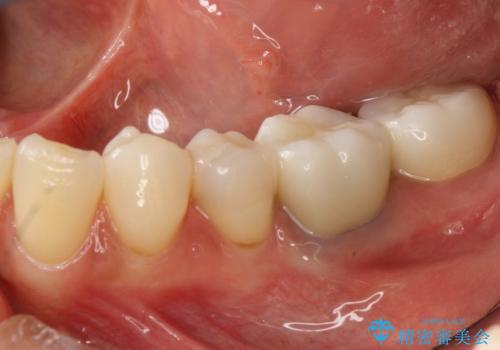

- 金属をセラミックにかえたいと来院されました。

左下6はメタルクラウン、左下7はメタルアンレーがあり、左下5には虫歯がありました。

左下5はセラミックインレー修復、左下6,7はオールセラミッククラウンにて修復していくこととしました。

左下6に関しては、メタルコアをファイバーコアへのやりかえ、やりかえの際根管の汚染が強かったため根管治療からやりなおすこととなりました。

見た目、使用感ともに満足していただきました。現在は他の部位も治療中です。